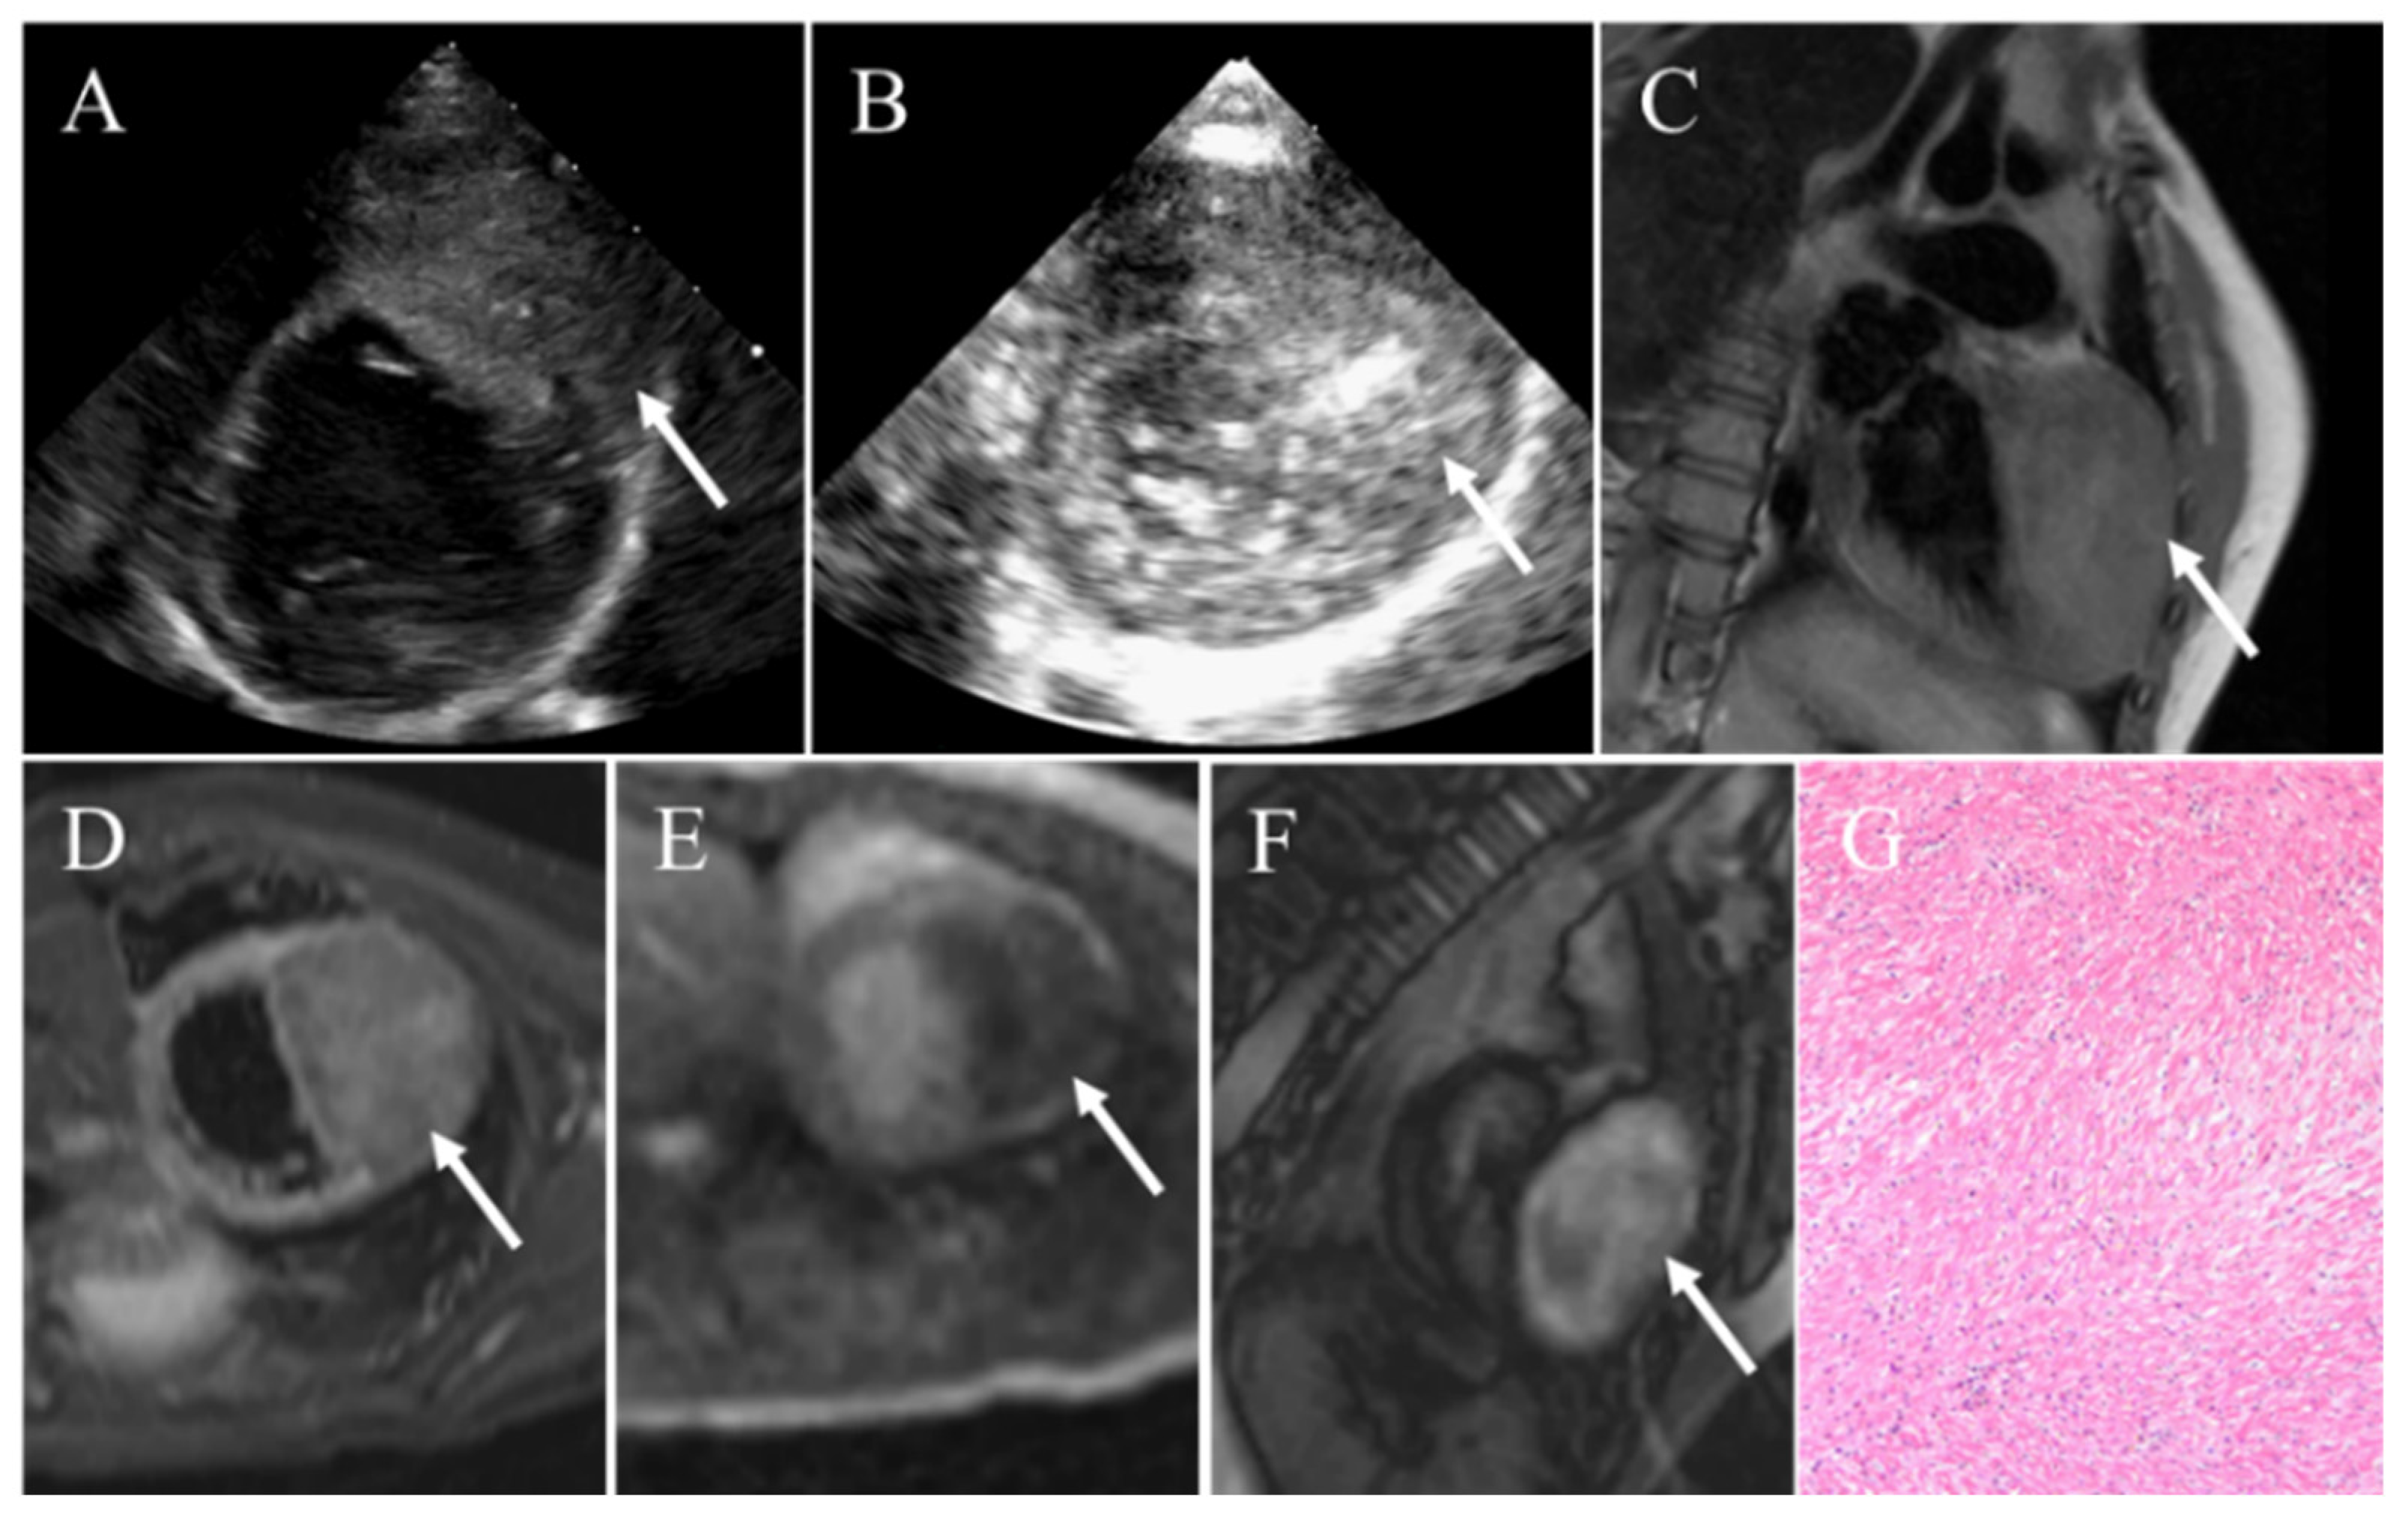

4.5. Fibroma

| Fibroma | Infants and children | No defined sex distribution | Ventricles | Large; intramural; well-circumscribed; noncontractile; central calcification | Homogenous; intramural; soft-tissue attenuation; central calcification; little to no enhancement | Iso-intense on T1WI; hypointense on T2WI; homogenous; no enhancement on resting first-pass perfusion imaging and EGE; hyperenhancement on LGE |

- Torimitsu, S.; Nemoto, T.; Wakayama, M.; Okubo, Y.; Yokose, T.; Kitahara, K.; Ozawa, T.; Nakayama, H.; Shinozaki, M.; Sasai, D.; et al. Literature survey on epidemiology and pathology of cardiac fibroma. Eur. J. Med. Res. 2012, 17, 5. [Google Scholar] [CrossRef] [PubMed]

- Araoz, P.A.; Mulvagh, S.L.; Tazelaar, H.D.; Julsrud, P.R.; Breen, J.F. Ct and mr imaging of benign primary cardiac neoplasms with echocardiographic correlation. Radiographics 2000, 20, 1303–1319. [Google Scholar] [CrossRef] [PubMed]

- Nwachukwu, H.; Li, A.; Nair, V.; Nguyen, E.; David, T.E.; Butany, J. Cardiac fibroma in adults. Cardiovasc. Pathol. 2011, 20, e146–e152. [Google Scholar] [CrossRef] [PubMed]

- Tao, T.Y.; Yahyavi-Firouz-Abadi, N.; Singh, G.K.; Bhalla, S. Pediatric cardiac tumors: Clinical and imaging features. Radiographics 2014, 34, 1031–1046. [Google Scholar] [CrossRef]